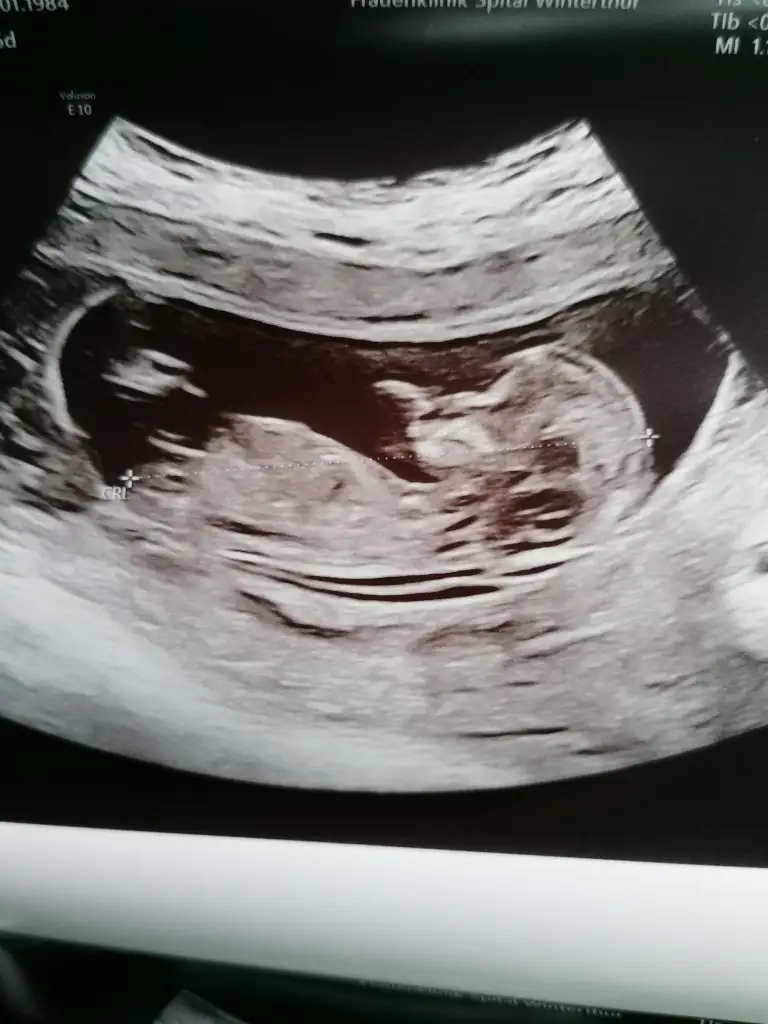

Yaaa maasallah kuzucugumaaa benimkine benziyor erkekmi acabaSelam kizlar ciktim kontrolden. Benim sipa büyümüs baya hickirip durdu. Ense kalinligi ve hersey cok iyi dedi dr yalniz bebegim 1 hafta önden gittigi icinn dogum tarihi 9 nisandan 2 nisana alindi erken döllenmeden kaynaklaniyormus.

Tanistirayim topikimizin ilk erkek bebegi sizi hic meraklandirmadan söylim dedim

Maşallah tosunumuza o zaman.. Gözün aydın her şey de güzel çıkmış. Cinsiyette belli. Ohh sefan olsun.Selam kizlar ciktim kontrolden. Benim sipa büyümüs baya hickirip durdu. Ense kalinligi ve hersey cok iyi dedi dr yalniz bebegim 1 hafta önden gittigi icinn dogum tarihi 9 nisandan 2 nisana alindi erken döllenmeden kaynaklaniyormus.